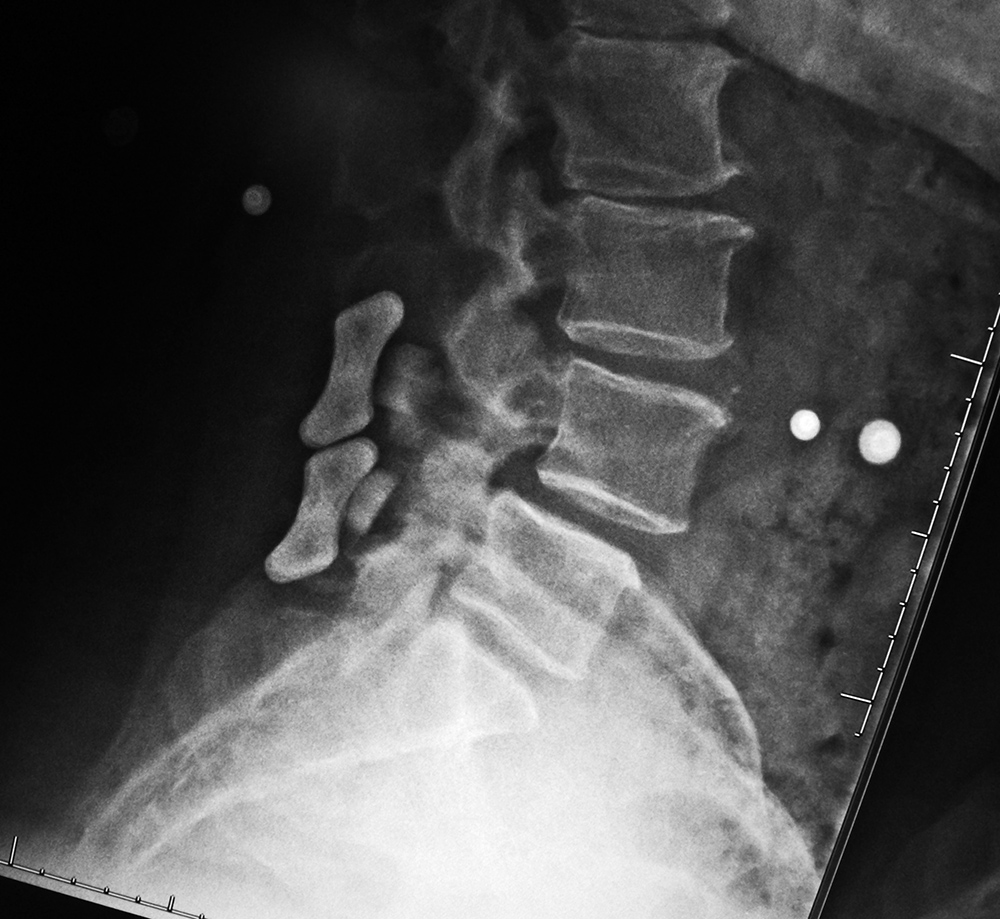

Lumbar spine bony disk strut, pedicle screws, and pedicle rods (lateral view) |